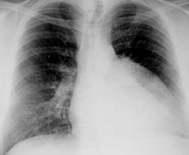

Cough and Dyspnea

Larry Hudgins, MD; Thomas M. Roy, MD; Said B. Iskandar, MD; Muhanad A. Al Hasan, MD; Vipul Brahmbhatt, MD

<div id="article-content-body"> <p><em><img alt="" src="/sites/default/files/images/ConCPEmpy3.jpg" style="border:1px solid black; height:139px;...